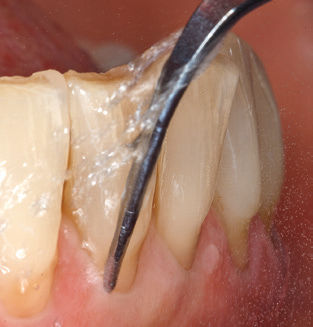

Of course, the use of instruments for mechanical removal of the biofilm is a central component of SPT and thus of primary significance. Consequently, the SPT workflow comprises both supragingival and subgingival cleaning. In our concept, a combination of hand instruments and machine cleaning has proven advantageous. A number of options are available for the mechanical procedures: sonic devices, ultrasonic devices and powder jet devices.

Although the fundamental principle of the ultrasonic devices remains, recent years have seen a whole host of further developments, resulting in an increase in efficiency, patient comfort and safety. These innovations are all present in the ultrasonic device (Tigon+, W&H Dentalwerk Bürmoos GmbH) currently employed by the authors, for example.

Good illumination of the working field facilitates the process considerably. The system used by the authors achieves this thanks to a 5x LED ring integrated in the handpiece. Naturally, a range of working tips for different indications is also offered. A straight, universally employable tip is the basic instrument required for machine cleaning of natural teeth (Fig. 5a and b). Curved tips, which allow access to exposed furcations, are also available for hard-to-reach areas in the posterior region (Fig. 6).

Of course, working tips for the cleaning of implant surfaces are also indispensable for SPT in patients fitted with implants. The implant cleaning attachment on the system used here is characterised by its tapered, hexagonal design. This design allows light, atraumatic penetration of the peri-implant pocket and displays a good cleaning performance (Fig. 7).

Fig. 4: Flexible probes with millimetre markings are recommended for the probing of dental implants (e.g. Colorvue Kit PCV11KIT6, Hu­Friedy). – Fig. 5a and b: A straight working tip (1P, W&H Dentalwerk Bürmoos GmbH) is a suitable instrument for use on all natural teeth. – Fig. 6: Curved working tips (3Pr/3Pl, W&H Dentalwerk Bürmoos GmbH) lend themselves to the processing of difficult-to-reach areas of the tooth and root surfaces (e.g. furcations). – Fig. 7: The tapered, hexagonal implant cleaning tip (1I, W&H Dentalwerk Bürmoos GmbH) permits atraumatic and efficient cleaning of the crown and abutment surfaces. – Fig. 8: Titanium and carbon curettes are suitable instruments for the manual cleaning of the implant surfaces.